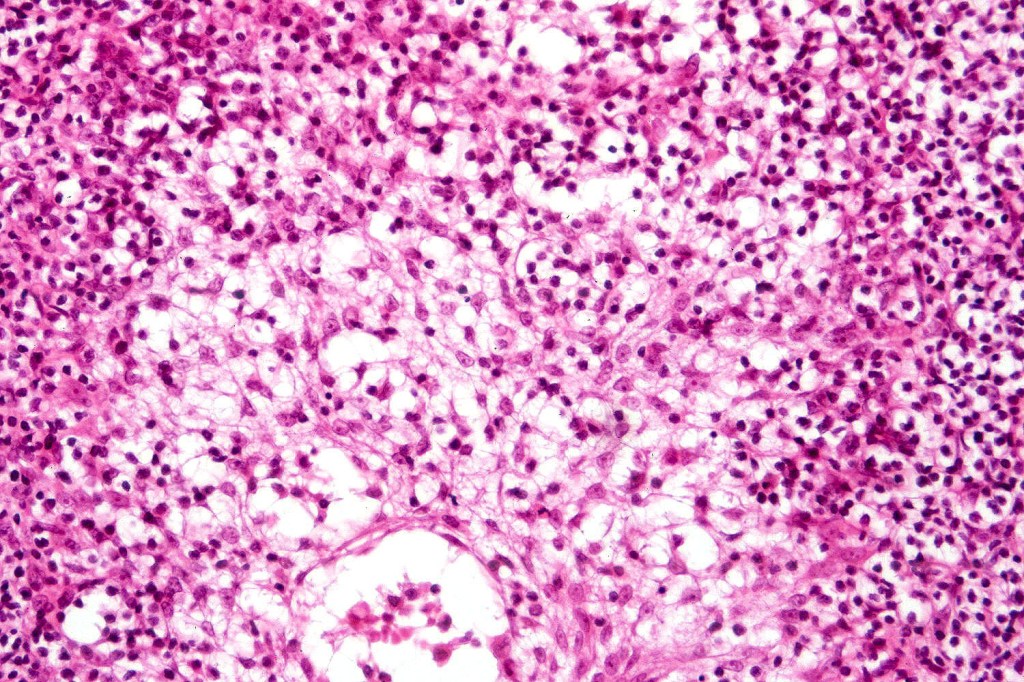

•Follicular infiltration by atypical lymphocytes & Sézary cells

•Eosinophils sometimes conspicuous (eosinophilic folliculitis-like appearance)

•Granulomatous inflammation secondary to follicular destruction